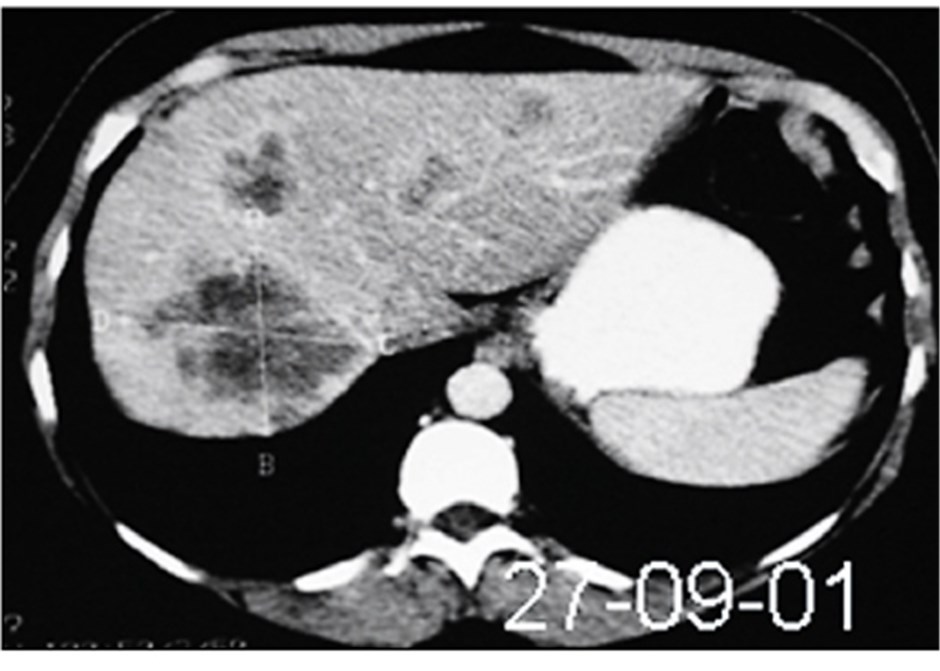

Source: soikeosonod.pages.dev Lebermetastasen multipel CT axial DocCheck , CEA-Wert bei Brustkrebs Bei der Verlaufskontrolle von Brustkrebs (Mammakarzinom) ist die alleinige Bestimmung des Tumormarkers CEA nur bedingt empfehlenswert . Bei Lebertumoren kann eine Bestimmung des CEAs eine Unterscheidung von gutartigen Lebererkrankungen/primären Leberkarzinomen (meist niedrigere Werte) und Lebermetastasen eines Darm- oder Bauchspeicheldrüsenkrebses (oft stark erhöhte Werte) ermöglichen.

Source: closeoneefz.pages.dev KMSonographie (CEUS) der Leber Ultraschall in der Hausarztpraxis , Niedrige AFP-Werte bei stark erhöhtem CEA-Werten deutet auf Lebermetastasen eines anderen Adenokarzinoms (vorwiegend aus Leber, Lunge, Brustdrüse) hin Bei Lebertumoren kann eine Bestimmung des CEAs eine Unterscheidung von gutartigen Lebererkrankungen/primären Leberkarzinomen (meist niedrigere Werte) und Lebermetastasen eines Darm- oder Bauchspeicheldrüsenkrebses (oft stark erhöhte Werte) ermöglichen.